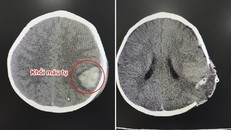

Bệnh viện Ðại học Y dược Shingmark (Đồng Nai) cho biết, đến ngày 1/6, tình trạng sức khỏe của cụ ông Lê Ngọc H (85 tuổi, ngụ tại xã Phước Tân, thành phố Biên Hòa) bị xuất huyết não rất nặng, liệt nửa người kèm theo nhiều bệnh lý khác đã qua cơn nguy kịch.

(Ngày Nay) - Các bác sĩ đã tiến hành phẫu thuật mở sọ não để lấy hết phần máu tụ sau đó xử lý các bệnh lý của cụ H. Ca phẫu thuật đã thành công, cụ H. đã khỏe lại.